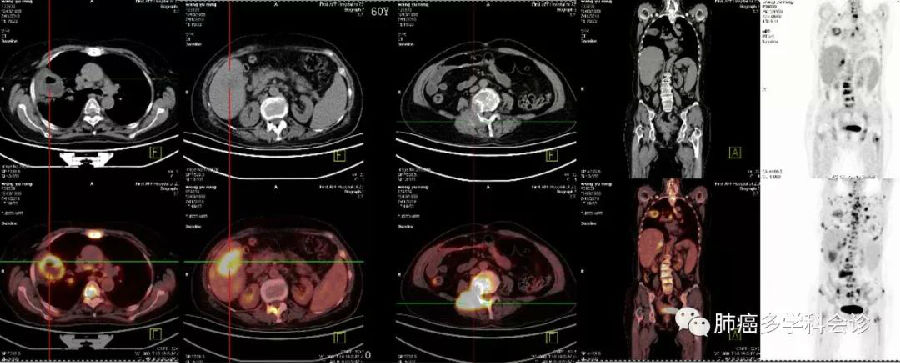

探案丨青年男性胸痛三月 Pet Ct显示肺结节和淋巴肿 腾讯新闻